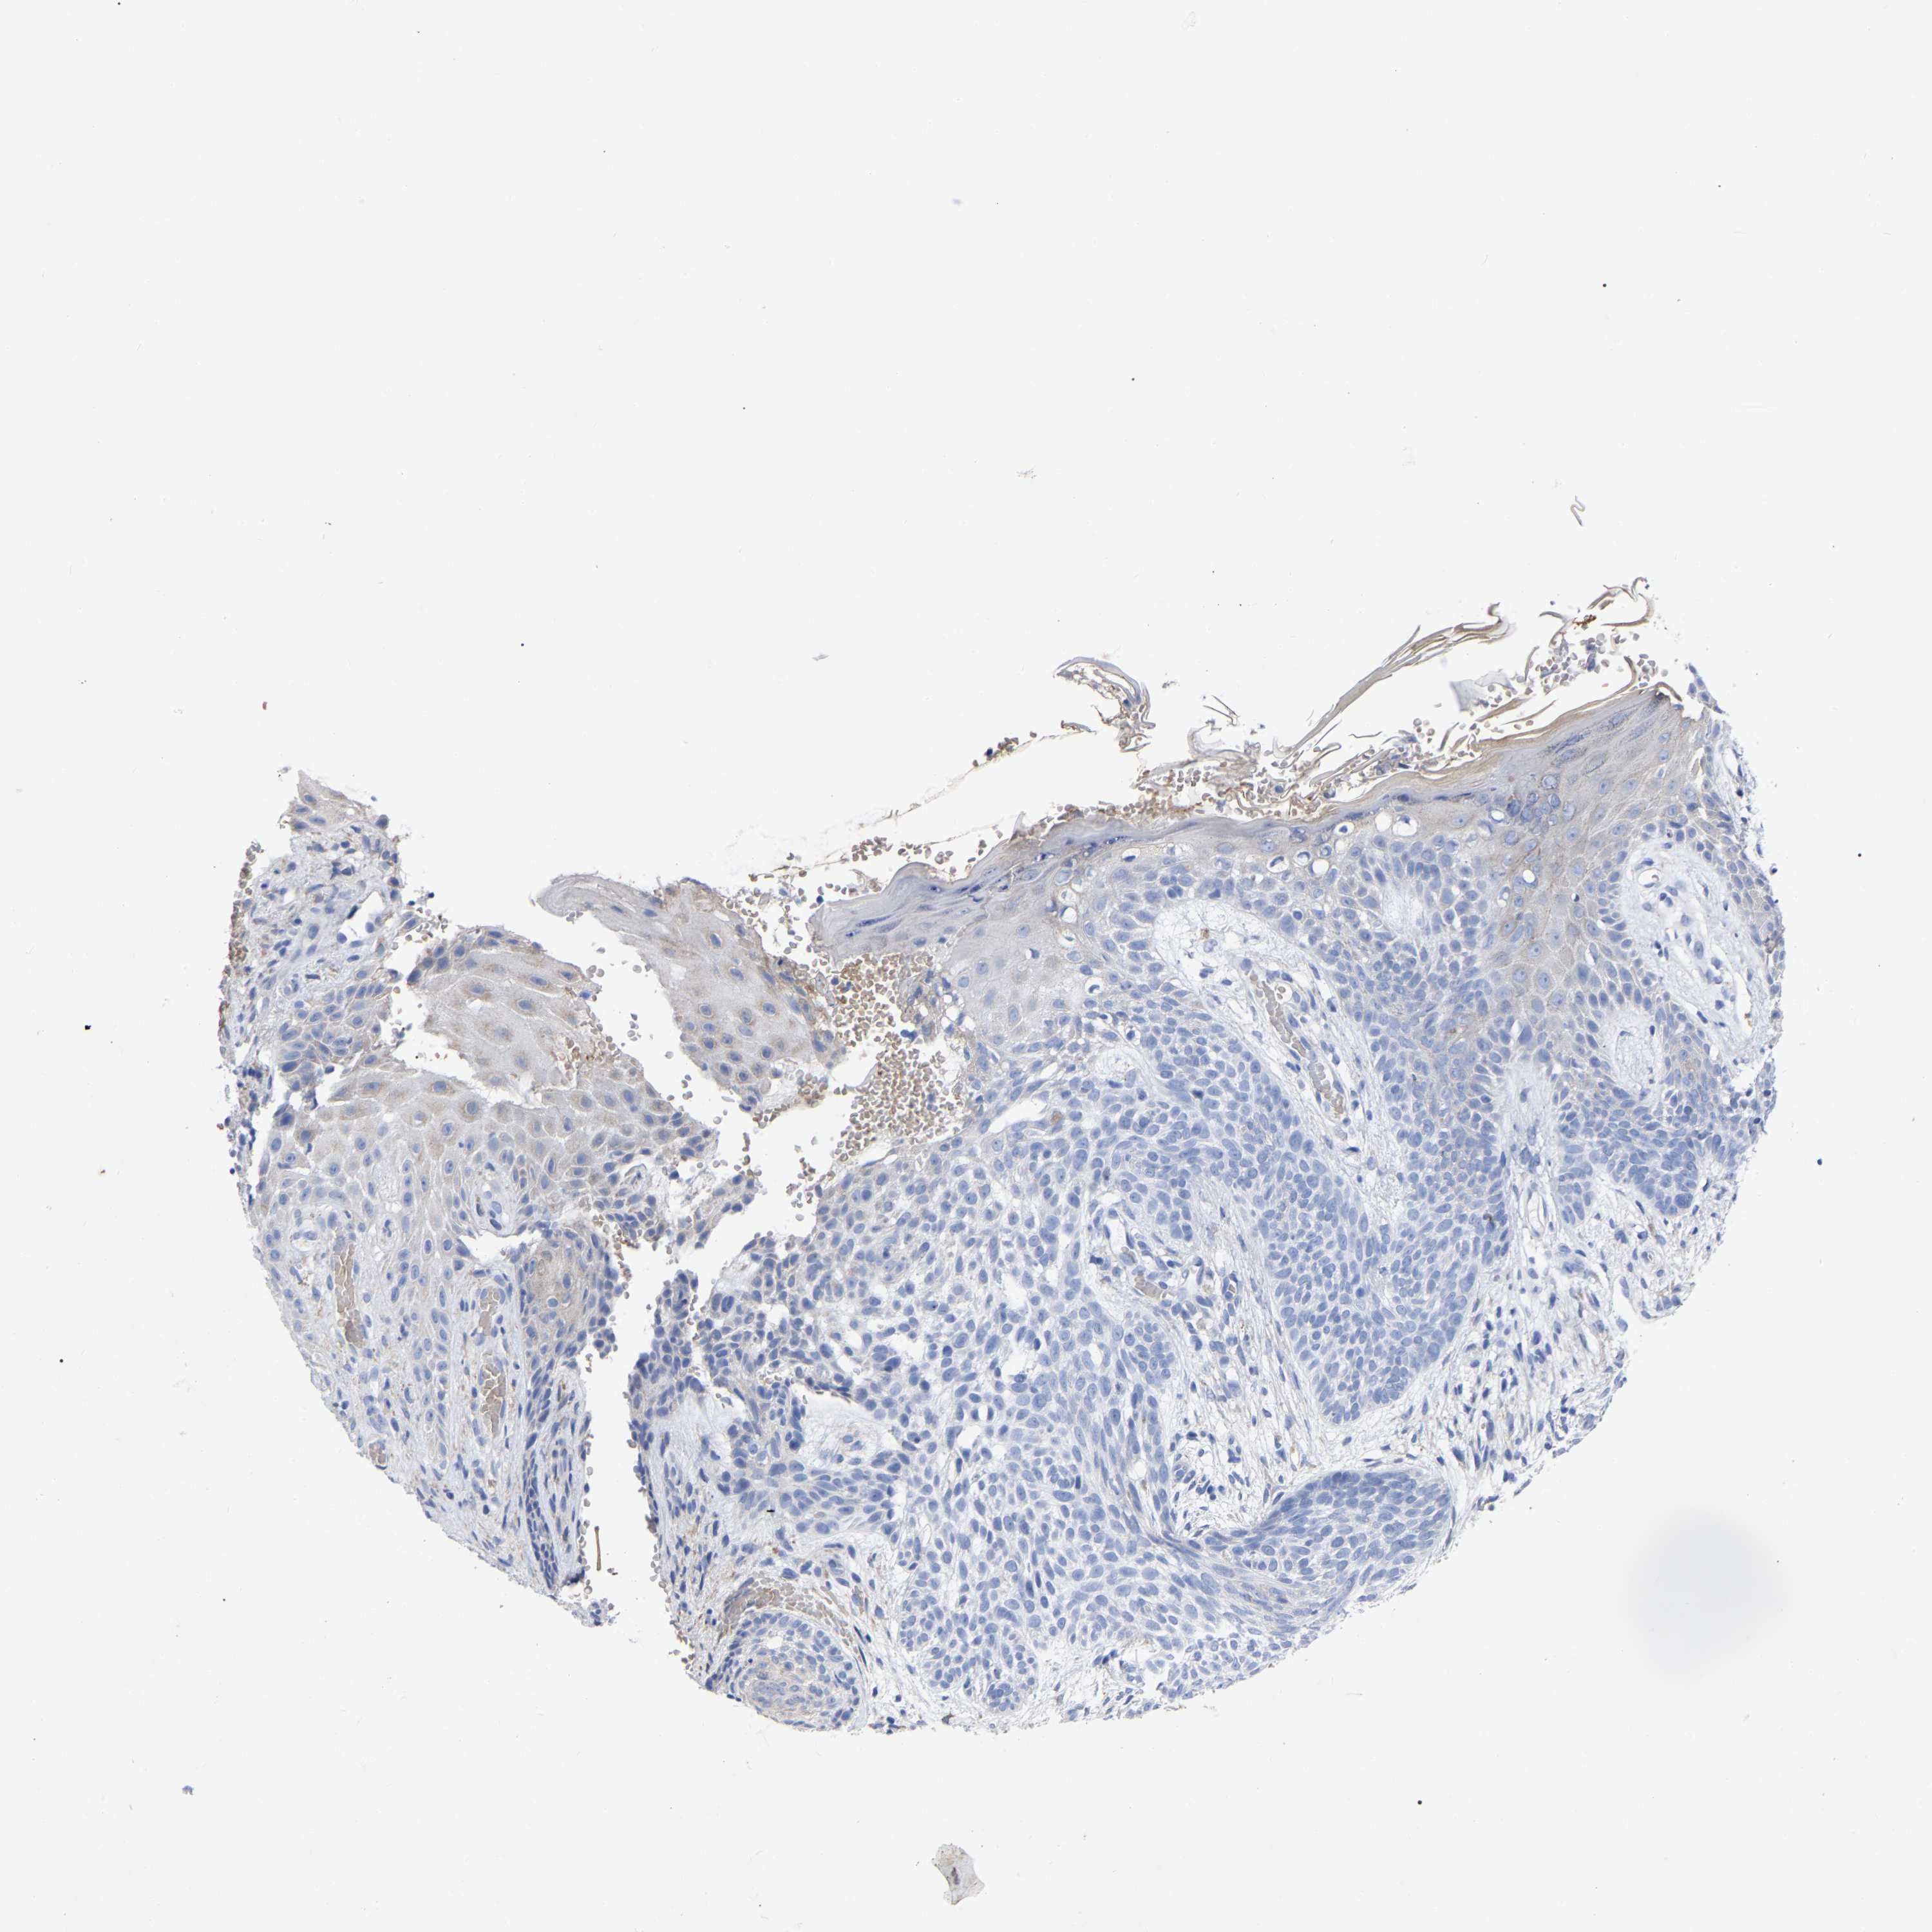

SKIN CANCER - Protein expressioni

A mouse-over function shows sample information and annotation data. Click on an image to view it in a full screen mode. Samples can be filtered based on level of antibody staining by selecting one or several of the following categories: high, medium, low and not detected. The assay and annotation is described here.

Each image is clickable and will lead to virtual microscopy that enables deeper exploration of all samples and also displays staining intensity scores, fraction scores and subcellular localization as well as patient and tissue information for each sample.

Antibody HPA018468

Squamous cell carcinoma, NOS